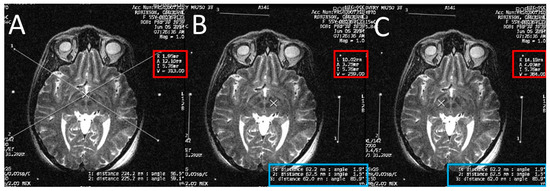

At the end of the scan, we chose the axial T2 image (or two adjacent images) in which the anterior commissure (AC) and the posterior commissure (PC) are identified (Figure 2). Then, we measured the distance between the middle and lower fiducials on both sides of the frame, and a maximum of 2 mm difference was allowed. The X and Y MR coordinate of the center of the frame was obtained at the point of meeting of two diagonal lines drawn on the MR console between the opposing anterior and posterior fiducials. After that, the X and Y MR coordinates of both the AC, the PC, and the center of the frame (Figure 3) were obtained from the MR console, and entered into a simple Excel worksheet (Microsoft, Redmond, WA, USA) designed by the senior author.

Calculating the anterior commissure (AC) and posterior commissure (PC) coordinates using the magnetic resonance scanner console. (A) Two diagonal lines intersecting at the center of the frame at the AC level with the magnetic resonance imaging (MRI) coordinates of the center of the frame shown inside the red square; (B) a crosshair at the posterior margin of the AC, with the MRI coordinates of the AC shown inside the red square. Two lines are drawn between the middle and the lower fiducials on both sides of the frame and their lengths (in the blue rectangle) are used to calculate the Z coordinate of the AC; (C) two diagonal lines intersecting at the center of the frame at the PC level with the MRI coordinates of the center of the frame shown inside the red square; (D) a crosshair at the anterior margin of the PC, with the MRI coordinates of the PC shown inside the red square. Two lines are drawn between the middle and the lower fiducials on both sides of the frame and their lengths (in the blue rectangle) are used to calculate the Z coordinates of the PC.